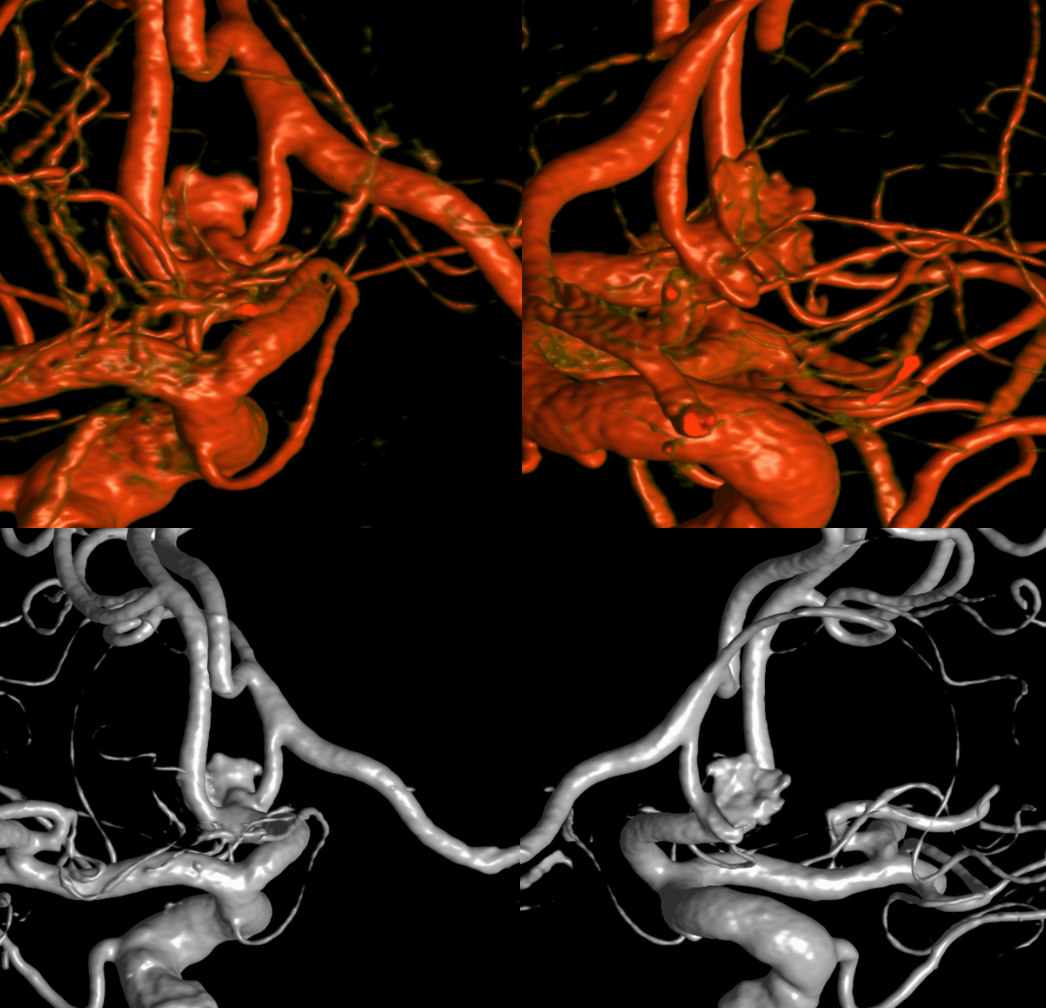

Stereo views of the two craniotomies, with translucent and sonolucent closure

Look at the difference in measurements after SBV 2 (top row) and SBV 1 (bottom row). Arrows point to location of the SVB 1 distal landing zone

One month later — only 1 mo. Aneurysm thrombosed. Right A1-A2 patent — can tell on MRA even with two SVBs

MRA

Robust bypass supports superior division and some more

No aneurysm, as suspected

Stereo pairs

Bypasses. Note A3-A3 patent bypass, as well as STA-MCA. Both seen thru radiolucent skull windows